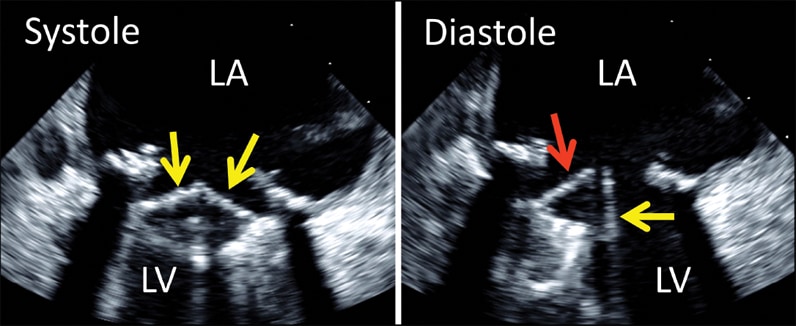

2-D transesophageal echocardiogram of bileaflet mechanical mitral valve prosthesis

2-D transesophageal echocardiogram of bileaflet mechanical mitral valve prosthesis

2-D transesophageal echocardiogram of bileaflet mechanical mitral valve prosthesis. Note both leaflets in closed position in systole (left, arrows), with opening of only one disk in diastole (right, yellow arrow). The red arrow denotes the fixed disk. LA, left atrium; LV, left ventricle.